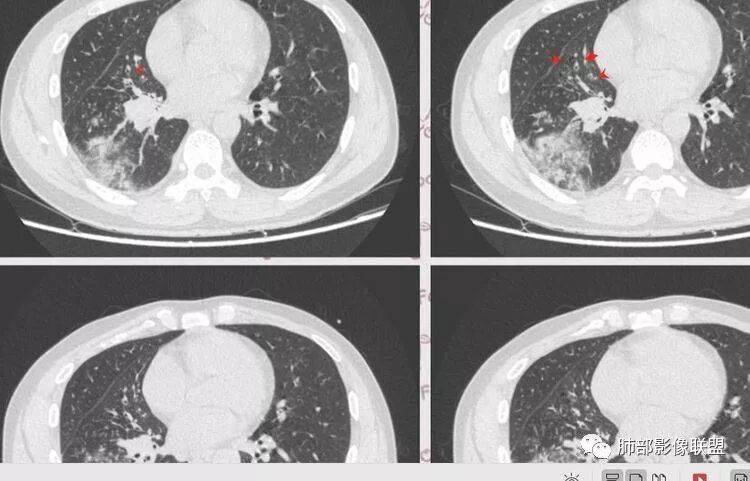

【影像资料】

张帅,首医附属潞河医院呼吸科:右肺下叶支气管开口明显狭窄,外基底段远端实变,内可见支气管征,周围可见弥漫结节样变,周围毛玻璃影,小叶间隔增厚,部分支气管壁不规则增厚,部分肺野可见小囊性变,壁部分增厚,右肺门明显增大,病灶与胸膜脂肪间隙增大,考虑恶性病变,腺癌。

王秀仙东宁市第二人民医院影像科:晨读:右肺下叶实变及磨玻璃影,边缘有收缩有膨隆,部分支气管进入扭曲扩张,磨玻璃影边缘清晰,实变影明显强化,内可见血管造影征,纵膈及肺门淋巴结肿大并强化,考虑粘液腺癌。

登封市三康医院(刘权威):右下肺肺不张,磨玻璃影,边缘清楚,空气支气管征,增强有强化,纵膈及右肺门淋巴结肿大并强化,考虑恶性肿瘤,粘液腺癌可能。

这是支气管扩张,老病灶,周围实变不明显,按理应该独立出来

下叶外基底段为主实变,周围GGO

分布:沿支气管段、亚段朝外蔓延分布

实变区边缘收缩,支气管走形自然

但是我们也可以看到实变区很多地方没看到支气管,也就是支气管在实变区分布不均匀,提示有些地方支气管腔内有物质填塞,显示不清

GGO边界大部分不清楚,内有树芽征,中央间质均匀增厚